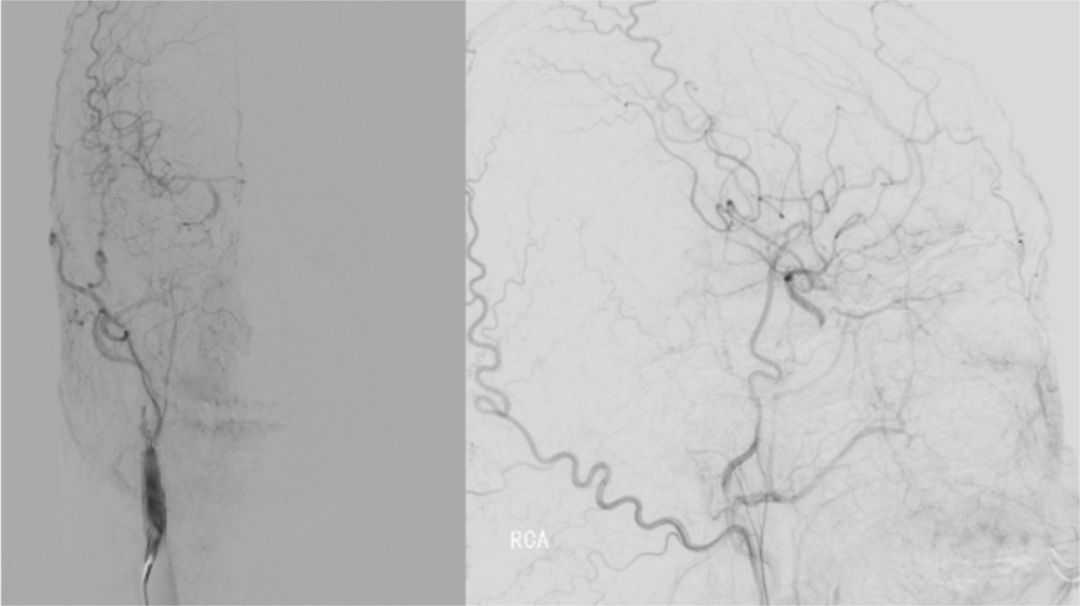

2019-06-07外院DSA:右侧颈内动脉闭塞(图2)。

图2

2019-07-05北京军颐中医医院高分辨核磁:

1.右侧颈内动脉夹层形成并血栓形成、管腔闭塞。

2.左侧颈内动脉眼段管腔中度狭窄,局部夹层不排除。

3.右侧大脑中动脉起始部管壁增厚,管腔重度狭窄(图3)。

图3